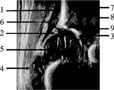

髋臼顶(acetabular roof):包括髋臼盂唇、髋臼软骨顶和髋臼骨顶(图1)。

髋臼软骨顶(cartilage acetabular roof):是指髋臼盂唇与髋臼骨顶之间的透明软骨区域(图1)。有人称为"软骨髋臼盖" [3,12]。

髋臼骨顶(bony socket):是从骨缘至髂骨下肢的区域,也就是髋臼骨顶"凹" ( concavity)(图1)。有人称为"骨性髋臼盖"[3,12],或"髂骨骨性髋臼顶"[13],有人称为"骨性髋臼窝"[14]。

髂骨下肢(lower limb):为髋臼骨窝最下缘(图1)。有人称之为髂骨下支[15],这种称法会与成人骨盆解剖中髂骨上、下支概念相混淆。有人称为"髋臼窝内髂骨下缘"[11,12],或为"髋臼窝内髂骨最低点"[7,16,17],或"髂骨下缘点" [6,13,14],或"髂骨骨化最低点" [8]。髂骨下肢内下方为Y形软骨。

骨缘区(bony rim area):为Graf法中图像分型中的"骨缘"。为与角度分型中的骨缘概念相区别,涂长玉等[10]将图像分型中"骨缘"称为骨缘区。骨缘区是指从髂骨向髋臼骨窝移行的区域(图1),即髂骨"凸" (convexity)。它包含了部分髂骨和骨缘。有人称为"骨性髋臼凸" [3,5,18];或"髋臼骨性突起" [19];或骨性髋臼缘[12];或"骨性髋臼外侧缘"[5,20]。

骨缘(bony rim):在Graf角度分型中,骨缘是髋臼骨窝最外侧的点(the most of lateral point of the concavity of the bony socket),是髋臼骨顶"凹" ( concavity)向髂骨"凸" (convexity)转变点[1],是指骨缘区内侧的"缺口",严格地讲是髂骨"凸"内侧缘的点。这里"凹"与"凸"是相对于髋臼窝而言。有人称之为骨性髋臼外侧缘[12];或为"骨化边缘" [16];